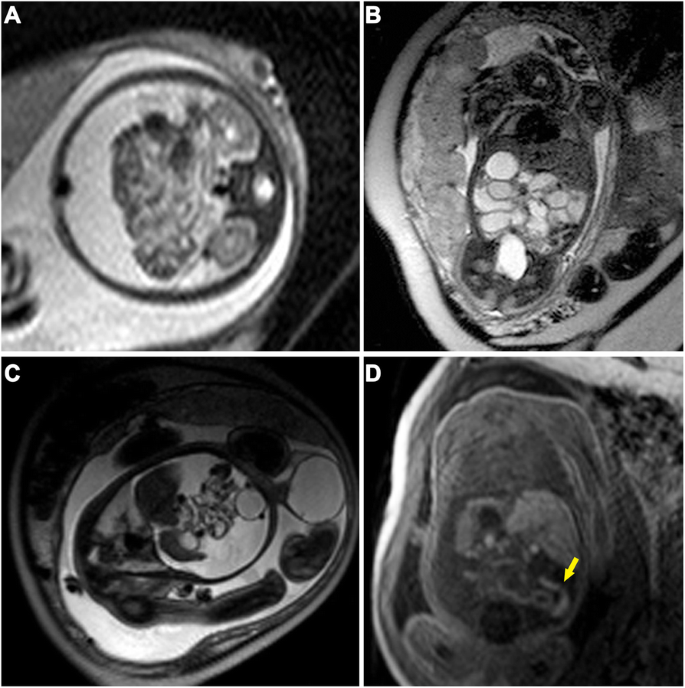

The imaging findings on both ultrasound and MRI are summarized in Table 1, and representative imaging findings are shown in Fig. 1 (ascites, gathered bowel loops, bowel dilatation, meconium pseudocysts, peritoneal calcification and hydroceles) and Fig. 2d (micro-colorectum). Ascites and bowel dilatation were two of the most common findings on both ultrasound and MRI. Distended bowel loops (27:4 on MRI or ultrasound), micro-colorectum (13:1), meconium pseudocysts (10:3) and hydroceles (13:4) were more likely to be depicted by MRI than by ultrasound. Of all 35 patients, 26 received surgical management. The intraoperative findings corresponded to the findings on MRI scanning. Atresia and perforation, two of the main causes of MP, were visualized in 22 and 12 infants, respectively.

Fetal MRI findings of meconium peritonitis in two fetuses receiving surgery. a-b A 30-week-old fetus with MP. A transverse 1.5-T T2-weighted image (TR = 15,000 ms, TE = 120 ms) indicates a large amount of ascites and gathering bowel loops (a) and dilated bowels (b). C-D. A 35-week-old fetus with MP. A sagittal 1.5-T T2-weighted image (c, TR = 15,000 ms, TE = 120 ms) reveals a high amount of free ascites in the peritoneal cavity, gathering and distortion of poor filled small intestines, and significant swelling in the left scrotum. A coronal T1-weighted image (d, TR = 234 ms, TE = 4.6 ms) shows distal micro-colorectum (yellow arrow)

To investigate the value of fetal MRI findings for predicting the need for surgical intervention, we divided all infants into an operative group and an observation group according to whether they received a postpartum operation, and we performed Fisher’s exact probability tests to analyze the correlations (Table 2). The presence of bowel dilatation (14/26, p = 0.048) and micro-colorectum (13/26, p = 0.013) seemed to be associated with the need for postpartum surgical intervention (Fig. 2). Of the 9 infants with nonsurgical interventions after delivery, 8 infants had ascites or/and distended bowel loops. There was only one infant with MRI signs of peritoneal calcifications or meconium pseudocysts who received conservative treatment (Fig. 3). Although the number of infants with meconium pseudocysts or peritoneal calcifications was not significantly different between the two groups, surgical intervention was considered when the MRI also revealed the presence of other findings other than ascites or distended bowel loops. Infants with hydrops in an enlarged scrotum did not need to undergo surgical treatment because of the self-healing capabilities of the body.

Fetal MRI findings of meconium peritonitis in two fetuses with existing cysts. a-b. A 34-week-old fetus received surgical intervention. A coronal T2-weighted image (a, SPAIR) reveals a cystic lesion in the left upper abdomen measuring 2.8 × 2.9 × 1.9 cm in size with a distinct thin border, linear-like incomplete separation and slightly high T2 signal inside. A transverse 1.5-T fetal T2-weighted image (b, TE = 15,000 ms, TE = 120 ms) shows that the bowel loops were pressed and shifted backward and dilated significantly with a diameter of 2.6 cm. c-d. A 27-week-old fetus received conservative treatment. A coronal T2-weighted image (c, SPAIR) shows a pseudocyst measuring 3.3 × 1.3 × 1.6 cm in size with irregular shape and high and slightly low T2 signal mixed inside. A transverse T2-weighted image (d, TR = 15,000 ms, TE = 120 ms) reveals a mild mount of ascites among bowel loops